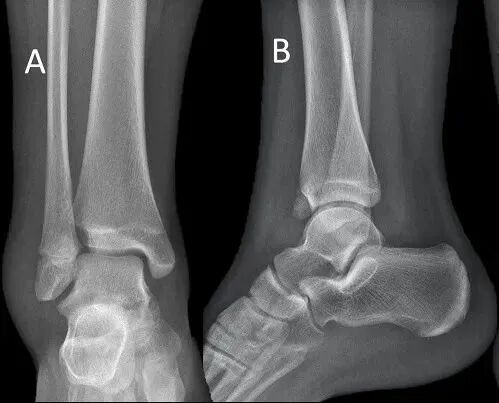

辅助检查上,由于Tillaux骨折片较小、X线片上有胫骨的遮挡以及临床医生认识不足,所以很容易被漏诊。一般来说,正位、侧位和踝穴位 X 片可发现移位超过 2 mm 的 Tillaux 骨折(在踝关节 X 片显示为 Salter-Harris III 型);但如果移位不大,X 片就极易漏诊。临床上对怀疑有该部位损伤时,应摄踝关节内旋30°~45°斜位X线片和CT片,CT 是评估 Tillaux 骨折及其移位程度的最佳术前手段,评估移位不大的 Tillaux 骨折更敏感。